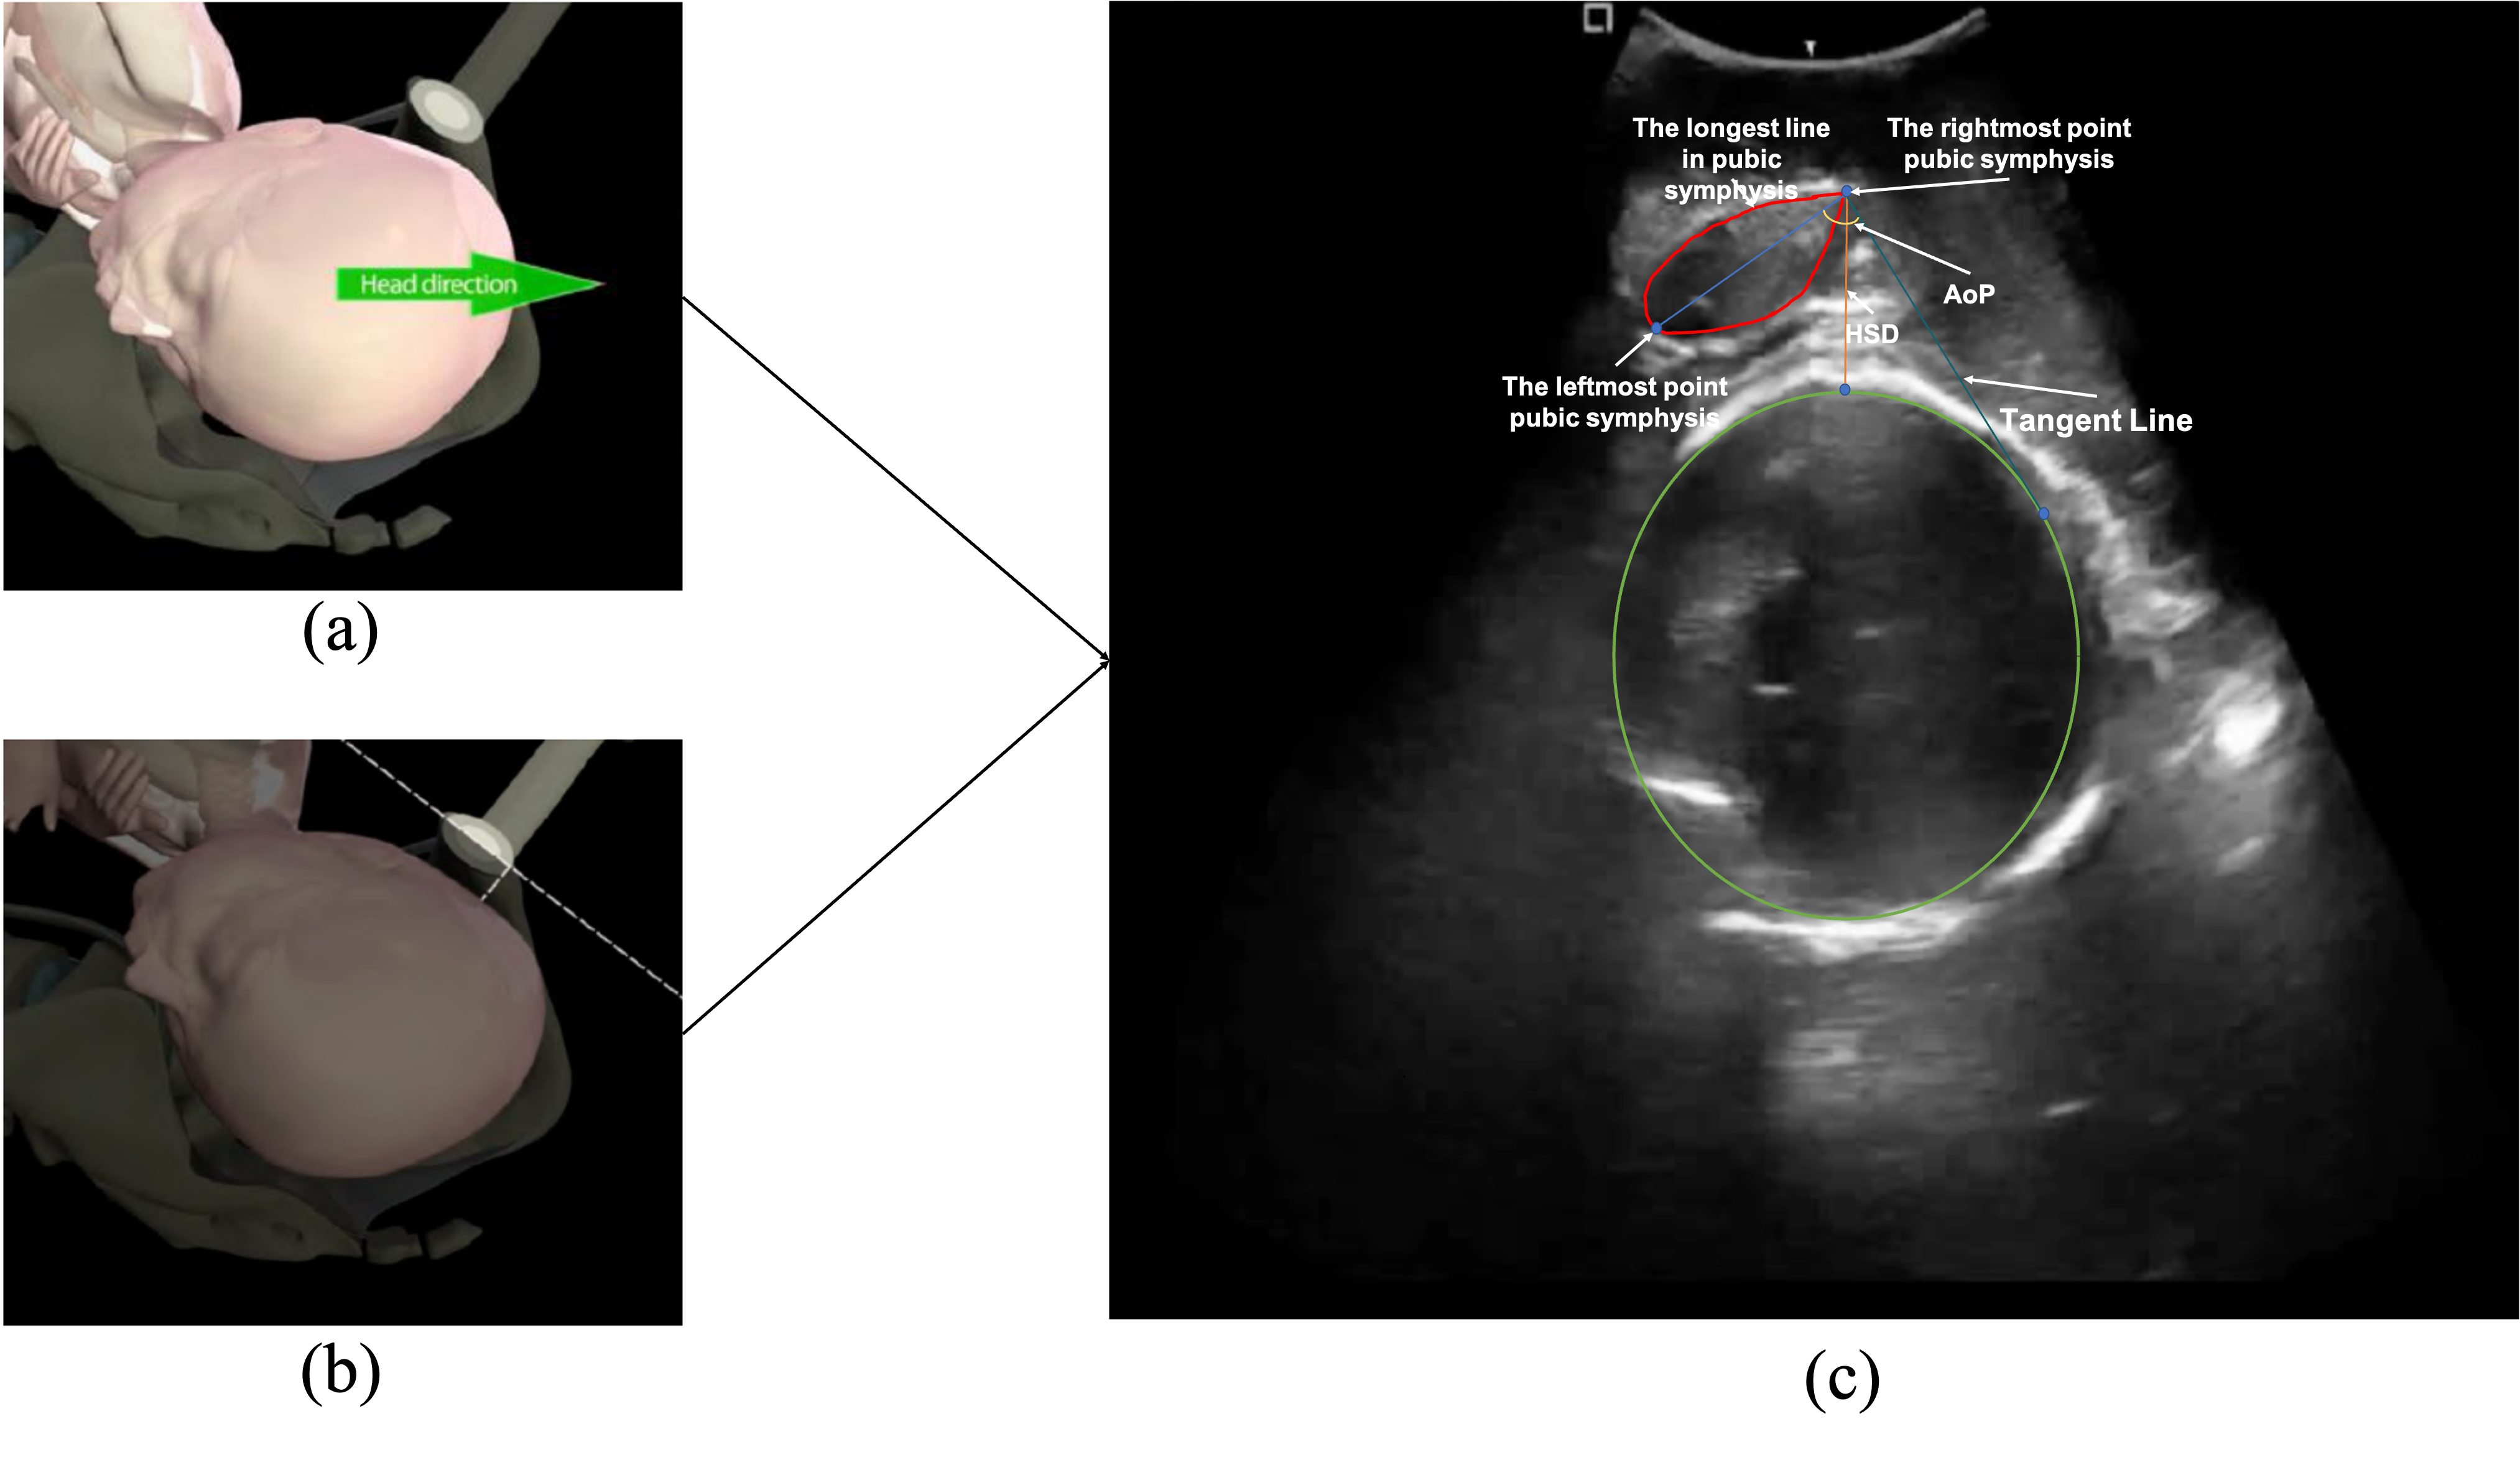

Ultrasound imaging provides real-time, non-invasive visualization of internal anatomy, proven to offer a higher degree of accuracy than digital palpation in monitoring fetal head descent. Multiple assessments are often required to track fetal head position, enabling timely diagnostics and interventions. According to the guideline from International Society of Ultrasound in Obstetrics and Gynecology (ISUOG), it highlights the Angle of Progression (AoP) and Head-Symphysis Distance (HSD) — derived from measurements of the fetal head and pubic symphysis — as key indicators for predicting successful instrumental delivery [1, 2, 3]. Notably, AoP is the angle between the pubic bone and lowest edge of pubis tangentially drawn to run along the deepest part of the fetal head [1, 4]. Specifically, there is an ultrasound probe that is placed on maternal suprapubic region to identify the fetal head. Landmarks to identify orientation such as fetal orbits or occiput are then noted. The fetal head midline features become difficult to determine transabdominally with fetal descent. A trans perineal approach is then recommended for precise determination of position. In this process, the pubic symphysis is used as a landmark for quantitive measurements. The process is illustrated in Fig. 1. Therefore, the structured approach can be formulated as a sequential process, including the identification of standardized ultrasound planes, the segmentation of anatomical structures, and the detection of key landmarks for precise measurement of AoP and HSD. The AoP and HSD are then derived based on the identified anatomical landmarks. The sequential process is essential for accurate and reliable measurements of AoP and HSD, as well as for the interpretation of the results. It enhances the robustness of the measurement process and improves the interpretability of the biometric assessment.